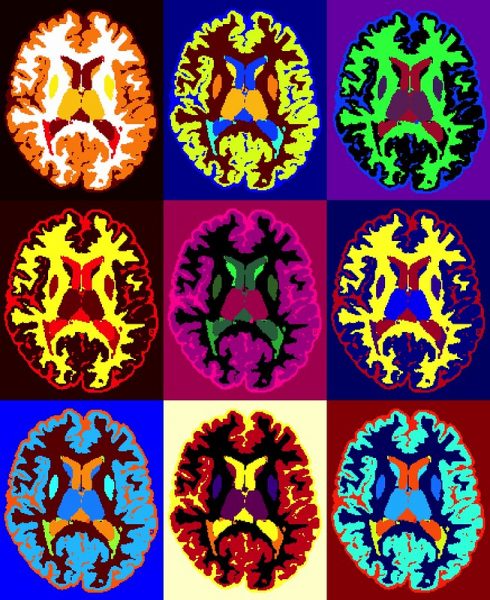

Κλινικά, η διάγνωση της πολλαπλής σκλήρυνσης στηρίζεται στη διαπίστωση αλλοιώσεων που εντοπίζονται σε διάφορα σημεία στο κεντρικό νευρικό σύστημα και οι οποίες έχουν προκύψει από περισσότερα από ένα επεισόδια. Οι αλλοιώσεις αυτές, μπορούν να επιβεβαιωθούν και από μαγνητική τομογραφία.

Σε κάθε κλινικό επεισόδιο, εμφανίζονται περίπου 10-20 βλάβες που απεικονίζονται στη μαγνητική και αφορούν το 90% των περιστατικών. Η παρουσία τους υποδεικνύει σχετικά πρόσφατη βλάβη, καθώς τα συμπτώματα υποχωρούν μέσα σε 4-6 εβδομάδες. Επιπρόσθετα, η μεγάλη έκταση των βλαβών στην μαγνητική και τα ευρήματα εγκεφαλικής ατροφίας σχετίζονται με μεγαλύτερους βαθμούς αναπηρίας. Η εξέταση του εγκεφαλονωτιαίου υγρού μπορεί να είναι χρήσιμη στη διάγνωση και να βοηθήσει στον αποκλεισμό άλλων παθήσεων που μπορεί να μιμηθούν την πολλαπλή σκλήρυνση.